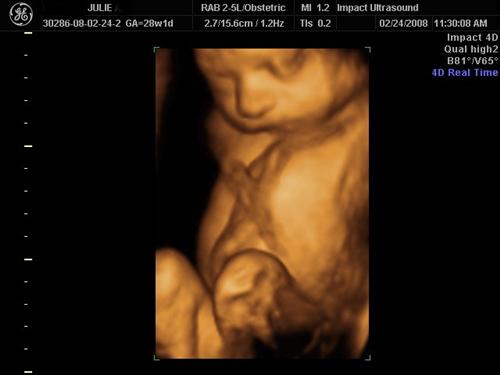

3D SONO PICS

Here is my He looks just like his daddy!

Cord around his neck I am bringing this to my next midwife appt!

Can see his boy parts between the legs

Again, notice the cord